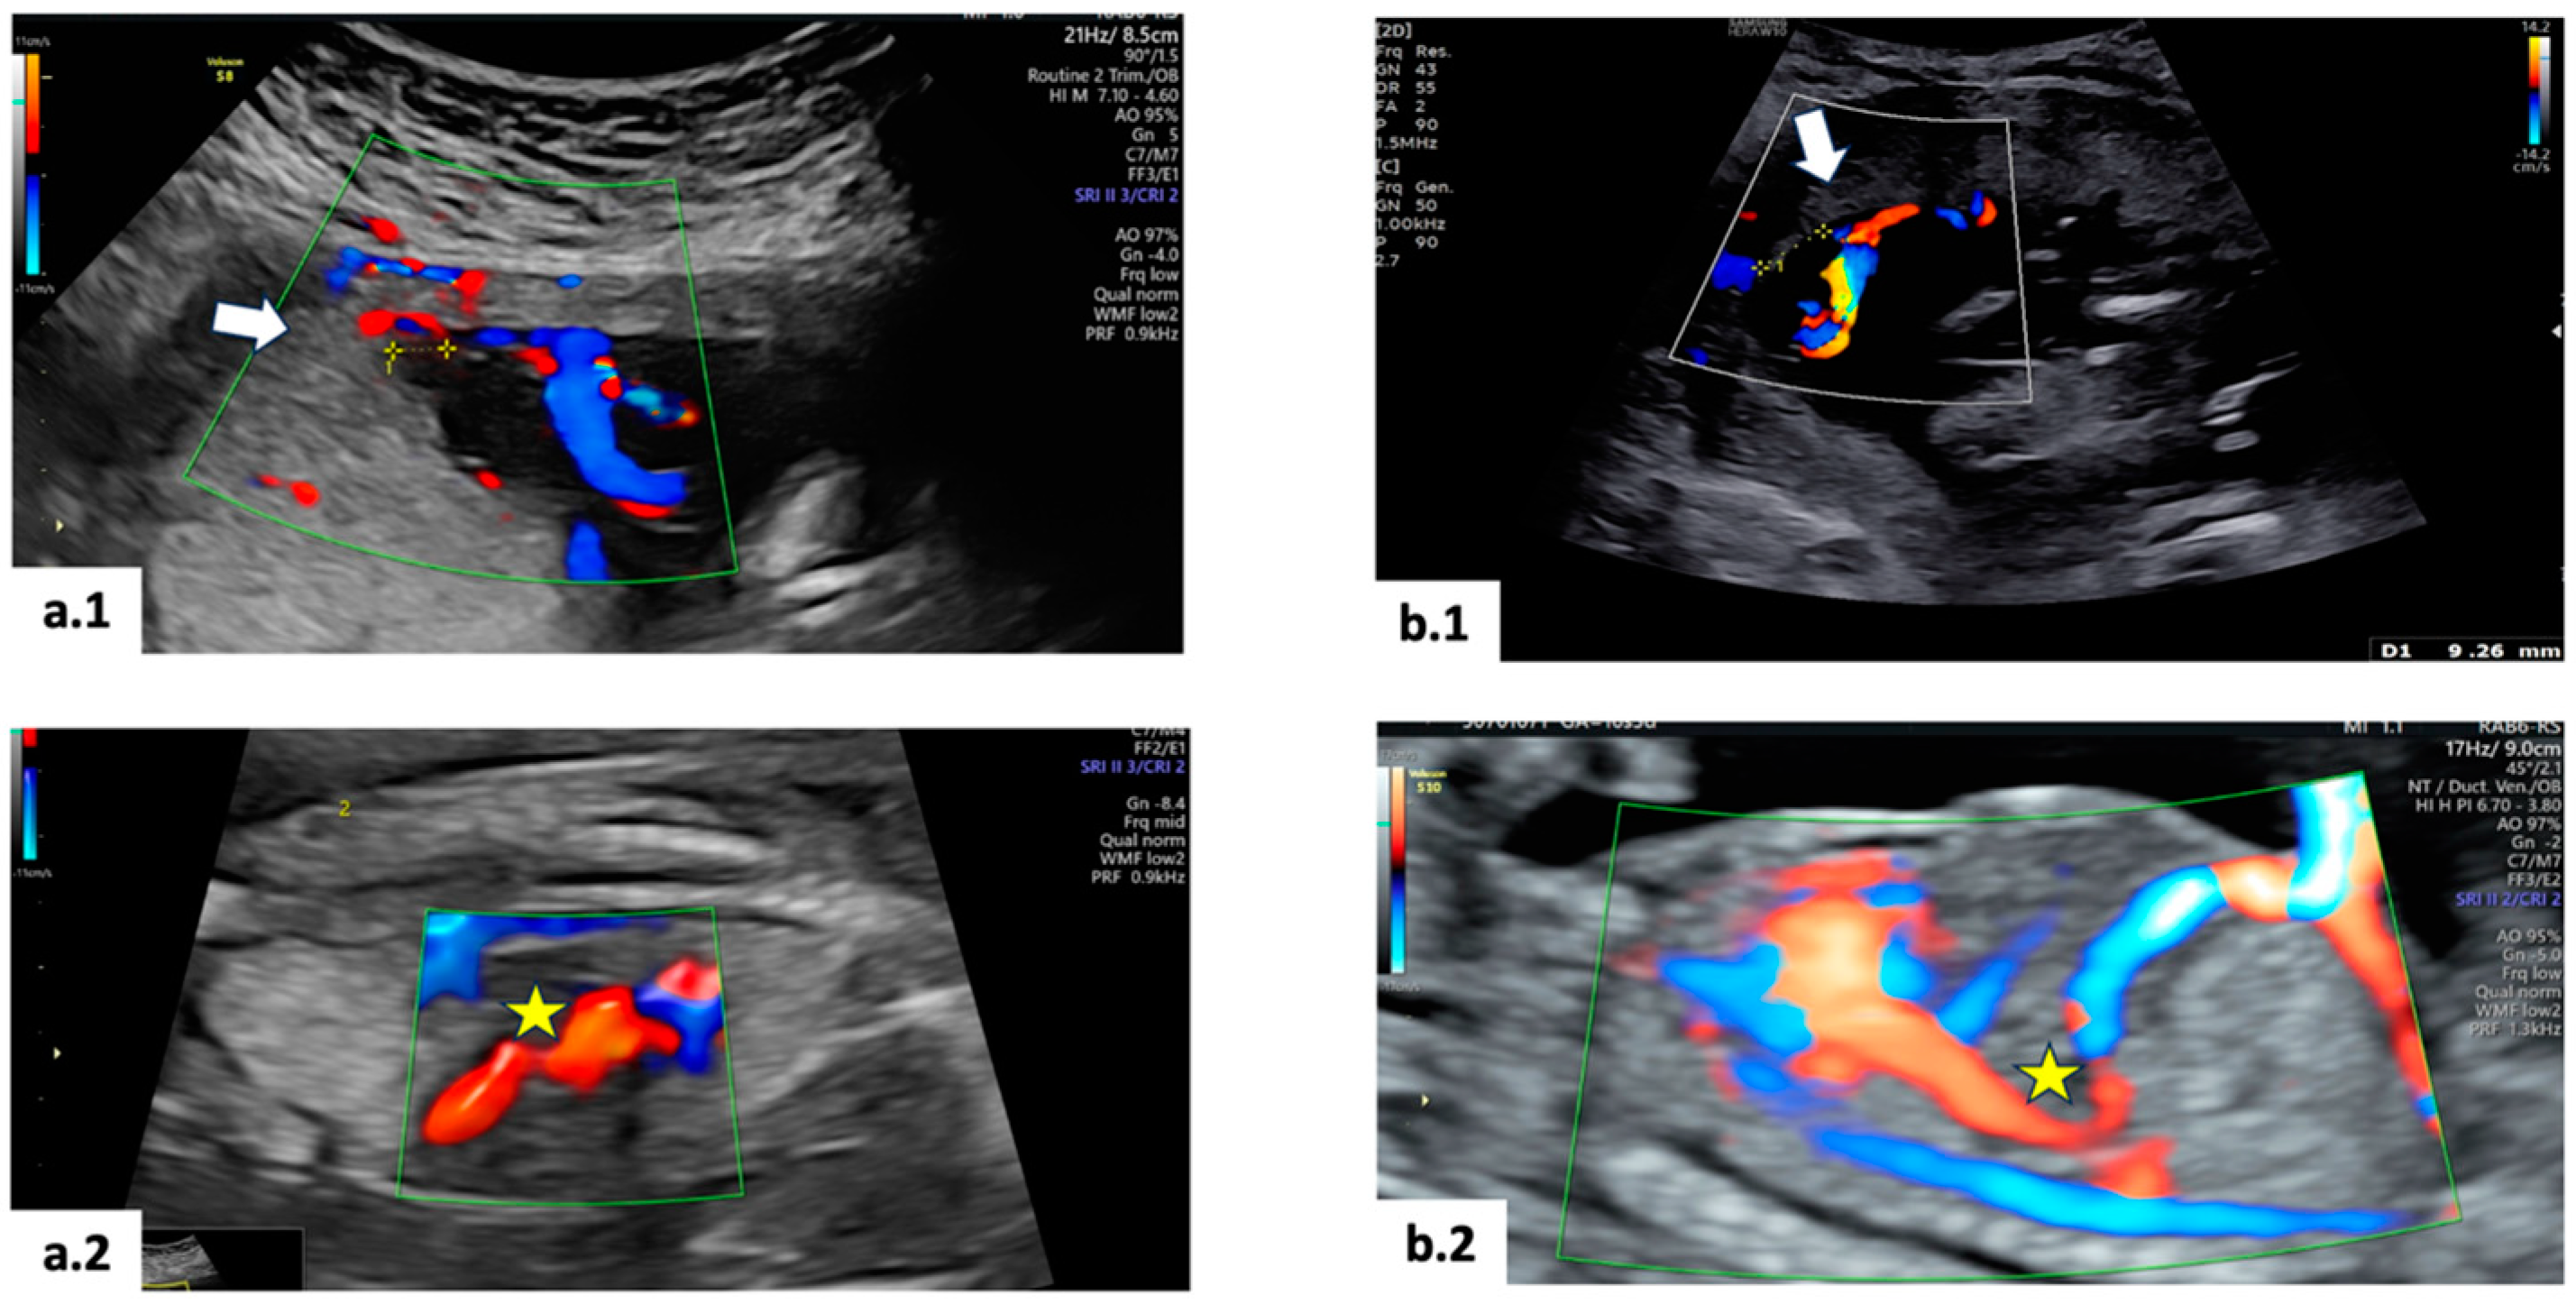

2. Case 1

3. Case 2